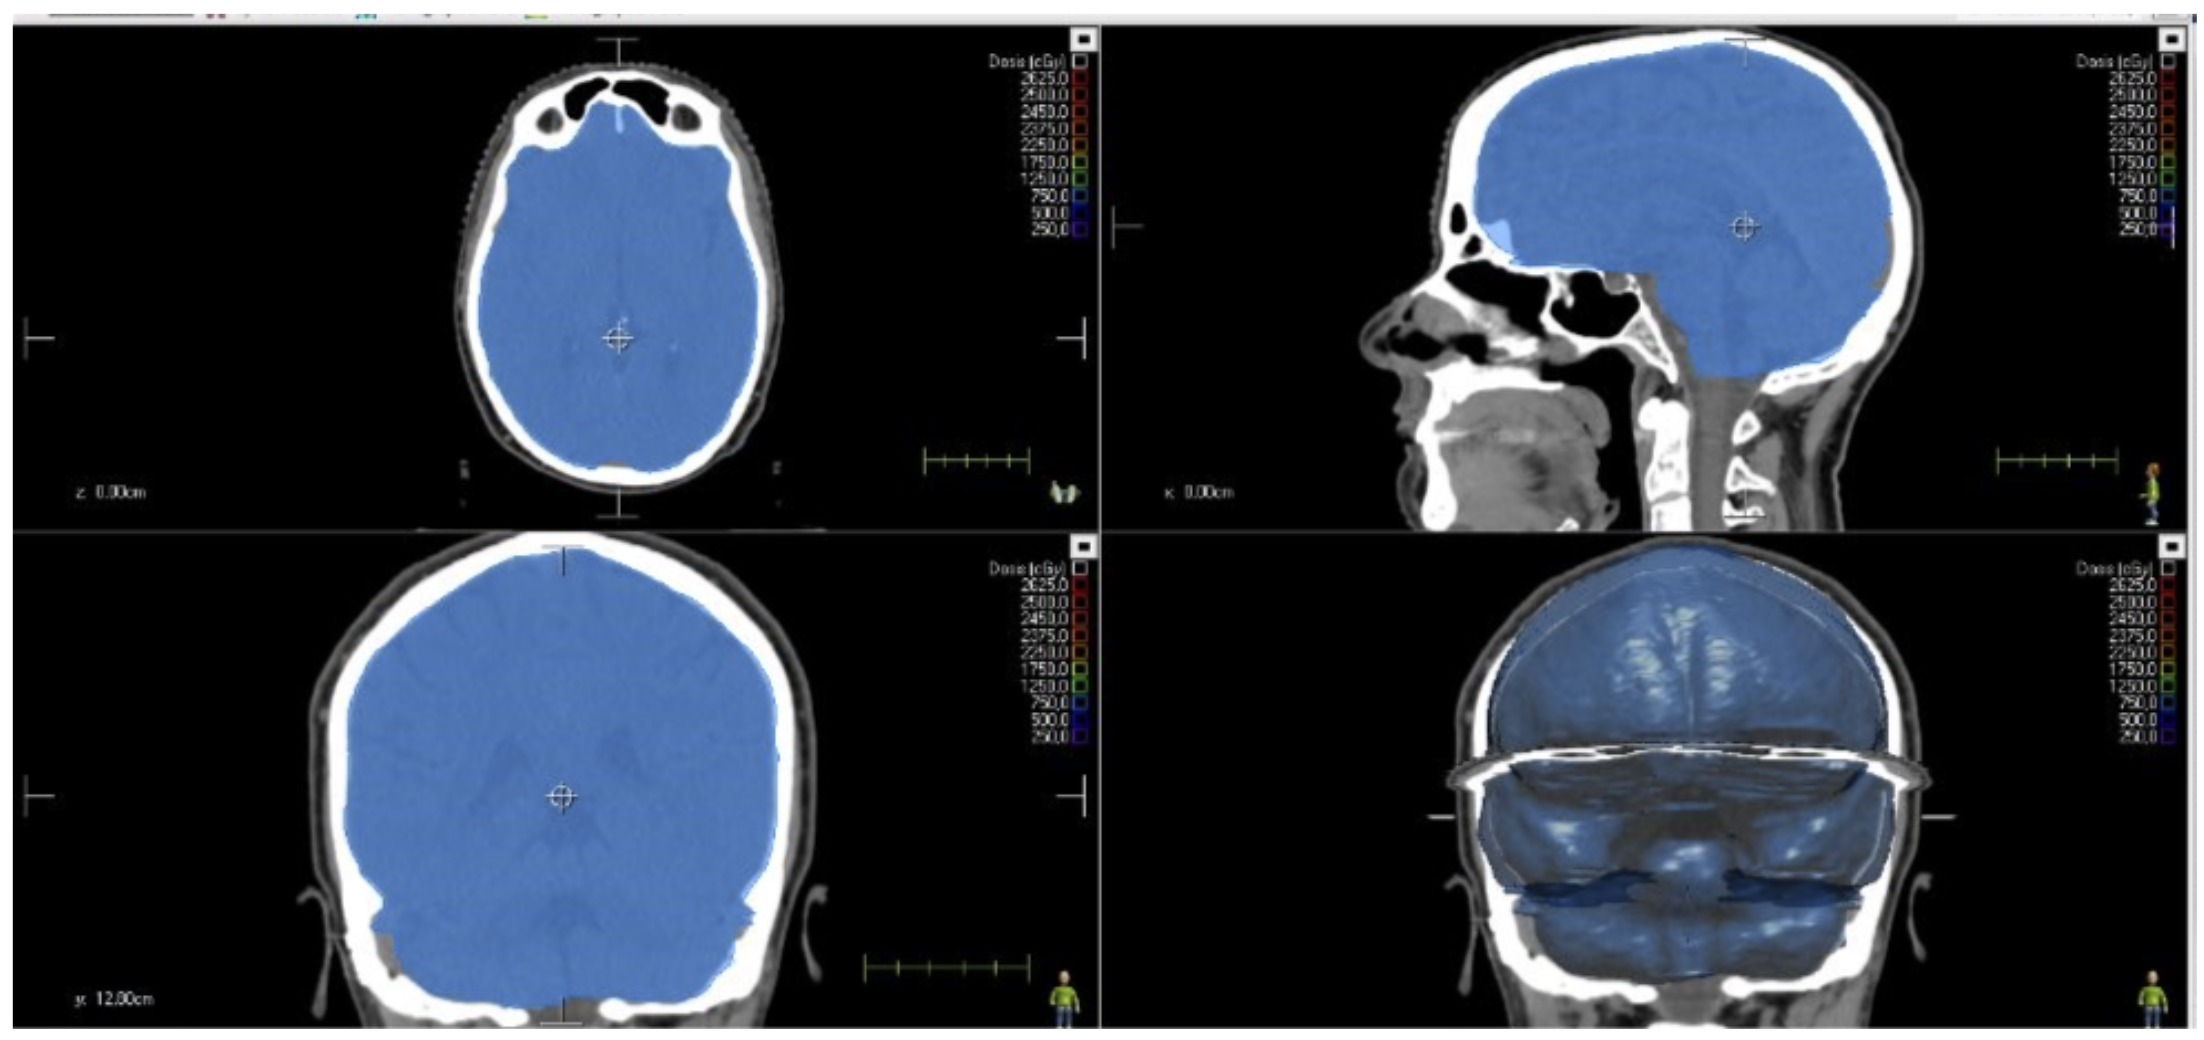

OAR-Train es la primera herramienta disponible en la plataforma e-learning AT Training Hub de Aplicaciones Tecnológicas S.A. Se dirige a los técnicos de Radioterapia y Dosimetría con el fin de capacitarlos en la correcta delimitación de OAR. Se trata de un codesarrollo con la Fundación para la Investigación Biomédica del Hospital Universitario Ramón y Cajal (FIBioHRC) y la Universidad Politécnica de Madrid (CTB-UPM). Por tanto, cuenta con su aval científico.

Con OAR-Train, los técnicos de Radioterapia y Dosimetría entrenan las habilidades de dosimetría y contorneo en un entorno seguro y realista. Además, mejoran la interpretación de imágenes clínicas y se familiarizan con las herramientas digitales que encontrarán en un hospital.